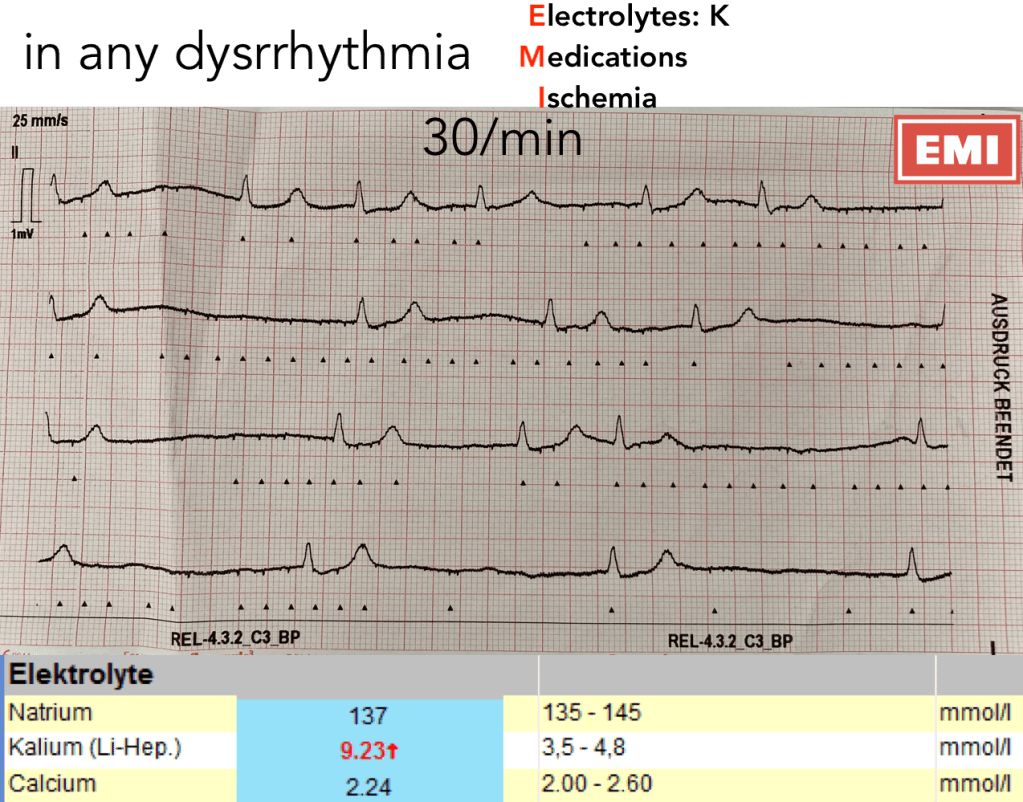

hyperkalemia

SOP Jena